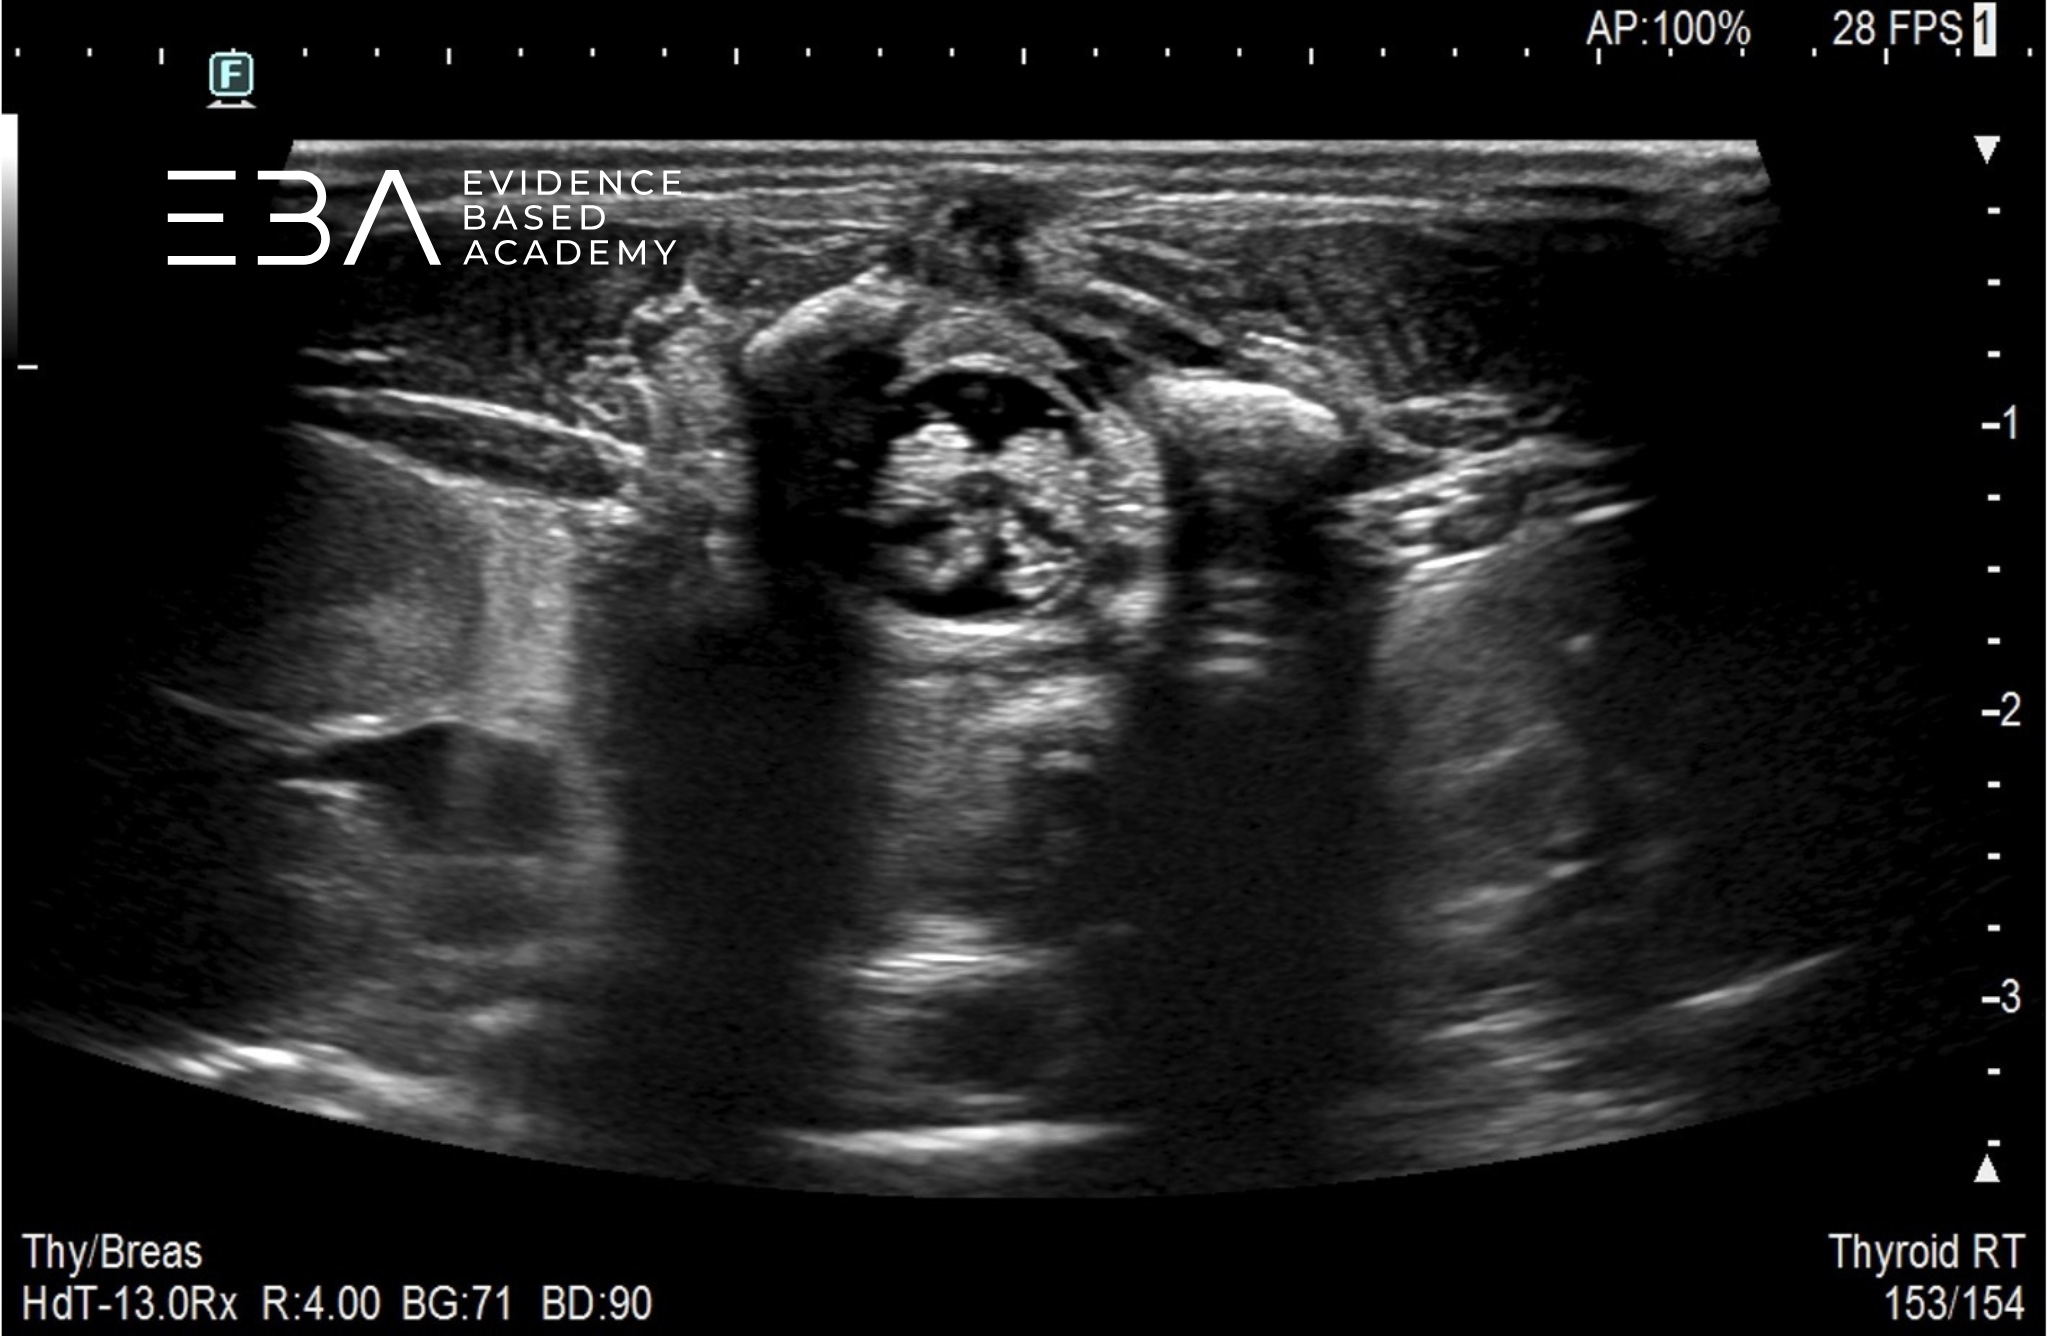

fot. 6

Przekrój poprzeczny kanału kręgowego na wysokości odcinka lędźwiowego.

fot. 7

Przekrój poprzeczny kanału kręgowego na wysokości drugiego kręgu lędźwiowego (L2) widoczny jest koniec stożka rdzenia kręgowego.